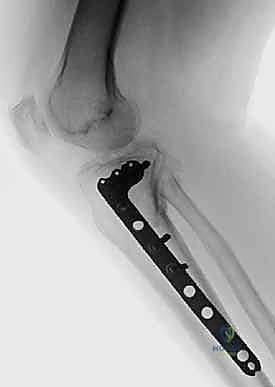

2. التثبيت الداخلي المفتوح (ORIF - Open Reduction and Internal Fixation)

هي العملية النهائية الحاسمة. تتضمن فتح الركبة، إعادة ترتيب الشظايا العظمية كقطع "البازل"، وتثبيتها باستخدام شرائح معدنية تشريحية ومسامير.

2. الشقوق الجراحية (النهج المزدوج - Dual Incision Approach)

لأن الكسر يشمل الجانبين الإنسي والوحشي، فإن شقًا جراحيًا واحدًا لا يكفي. يقوم الدكتور هطيف عادة بعمل شقين منفصلين لضمان عدم سلخ مساحة كبيرة من الجلد وتقليل خطر النخر:

* شق أمامي وحشي (Anterolateral Incision): للوصول إلى اللقمة الوحشية (التي تكون غالبًا مفتتة ومنخسفة).

* شق خلفي إنسي (Posteromedial Incision): للوصول إلى اللقمة الإنسية الك